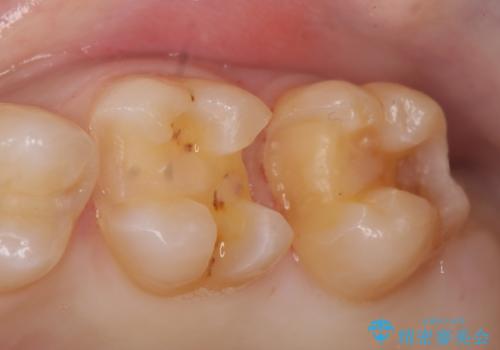

- 左上奥歯がしみるといらっしゃった方の症例です。

左上7近心の虫歯は歯茎より深く、歯茎を下げるため歯周外科を行いました。

術後歯肉の回復を待ち、左下6、7ともにセラミックインレーによる修復を行いました。